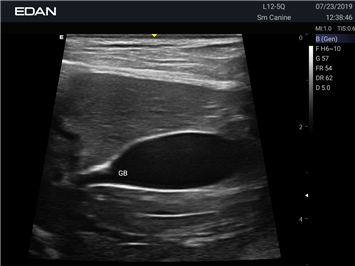

Ветеринарный ультразвук одним нажатием. Система Acclarix AX2 VET разработана с целью обеспечить бескомпромиссную производительность по доступной цене. Наличие уникальных двойных аккумуляторов в легком корпусе массой 4,5 кг из магниевого сплава позволяет системе Acclarix AX2 VET удовлетворять все потребности ветеринарных исследований, сохранив низкую стоимость.

EDAN Acclarix AX2 VET представляет собой специализированную ветеринарную ультразвуковую систему, сочетающую высокую производительность с доступной ценой. Благодаря продуманной конструкции и передовым технологиям, система обеспечивает качественную диагностику животных различных видов.

• Высокое разрешение для детальной диагностики

• Улучшенная визуализация глубоко расположенных органов

• Непрерывная автоматическая оптимизация изображения

• Адаптация к особенностям анатомии разных видов животных

• Повышенная точность исследований

• Предустановленные протоколы для различных видов животных